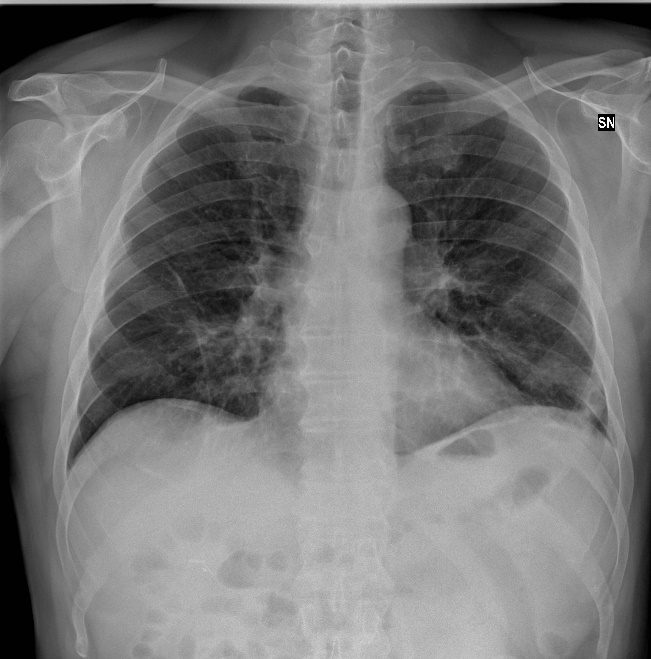

assets/ex-covid.jpegpython inference.py \ --weightspath models/COVIDNet-CXR4-A \ --metaname model.meta \ --ckptname model-18540 \ --imagepath assets/ex-covid.jpeg次のような結果が表示されます。

Prediction: COVID-19 Confidence Normal: 0.031, Pneumonia: 0.189, COVID-19: 0.780正常 0.031、肺炎 0.189、COVID-19 0.780 でありCOVID-19の可能性が高いという判定結果です。

Geographic severity: 0.519 Geographic extent score for right + left lung (0 - 8): 4.155 For each lung: 0 = no involvement; 1 = <25%; 2 = 25-50%; 3 = 50-75%; 4 = >75% involvement. Opacity severity: 0.388 Opacity extent score for right + left lung (0 - 6): 2.329 For each lung: 0 = no opacity; 1 = ground glass opacity; 2 =consolidation; 3 = white-out.判定の正確な定義はわかりませんが、involvement=浸潤、consolidation=濃い浸潤影 でしょうから、中等度に陰影が広がっているという感じでしょうか。